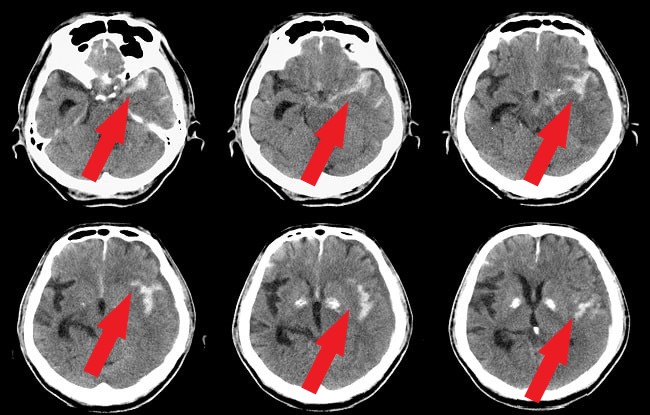

Gambar 2. CT scan kepala non kontras SAH

CT Scan Kepala Nonkontras

Pemeriksaan CT scan kepala harus segera dilakukan pada pasien dengan kecurigaan SAH. CT scan yang dilakukan dalam waktu 6 jam sejak onset memiliki angka sensitivitas 100%. Jika pemeriksaan ini dilakukan dalam rentang waktu 72 jam maka memiliki angka sensitivitas 97%. Selanjutnya, jika dilakukan setelah hari ke-5 akan memiliki sensitivitas semakin rendah, yaitu hanya 50%.[4,6]